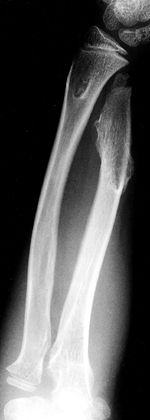

The long bones are thin and osteopenic. The femur may have a

“concertina” appearance, that is, a crumpled shape due to multiple

fractures. There is widening of the metaphyses, and growth arrests may

occur. Irregular calcifications may extend into the metaphysis, a

condition referred to as “popcorn epiphysis” (Fig. 180.10).

![]() |

|

Figure 180.10.

Severe bowing, multiple healed fractures, and epiphyseal calcifications in the lower extremity of a child with severe osteogenesis imperfecta. |